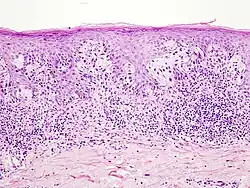

- Окончательный диагноз меланомы может быть установлен только после гистологического исследования, проведённого после тотального удаления невуса (опухоли) с достаточным захватом здоровых тканей. Предоперационная биопсия с помощью иглы или частичного удаления противопоказана, во избежание распространения меланомы. Определяется глубина прорастания (Clark, Breslow) и митотический индекс.

Стадии меланомы кожи

Микростадии по Clark 1967 г.

- Уровень I: все опухолевые клетки находятся в эпидермисе, до базальной мембраны

- Уровень II: клетки опухоли инфильтрируют сосочковый слой дермы

- Уровень III: опухоль достигает границы между сосочковым и сетчатым слоями дермы

- Уровень IV: опухолевые клетки обнаруживаются в сетчатом слое дермы

- Уровень V: опухоль прорастает в жировую клетчатку

Клеточный состав меланомы не влияет на клиническое течение опухолевого процесса, однако такие признаки, как митотический индекс, уровень инвазии в дерму, изъязвление и некоторые другие, имеют прогностическое значение. Глубина инвазии меланомы остаётся лучшим прогностическим показателем. На этом основан расчёт пятилетней выживаемости больных с этим новообразованием (англ. Five Year Survival FYS).